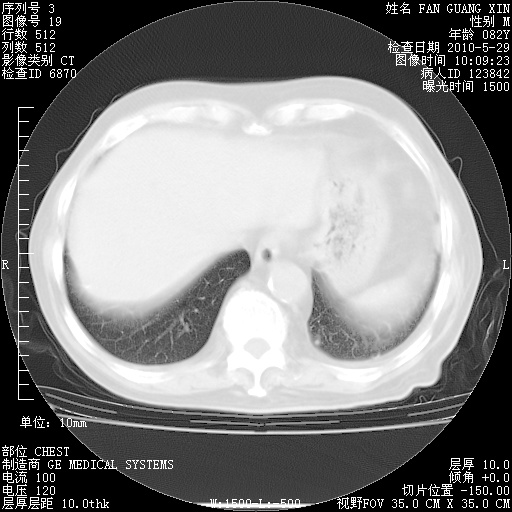

再治疗10天后的肺部CT

再治疗10天后的肺部CT 纵膈窗

阅读此次胸部CT,肺间质渗出性改变较入院时有吸收。目前从体温、白细胞、中性分叶明显增高,肯定存在细菌感染(发生医院感染哦,若无消化道及泌尿系统等感染的依据,肺部感染可能大)。若你院头孢哌酮舒巴坦钠耐药率较高,同意你的方案,若48小时体温仍高,可考虑使用碳青霉稀类抗菌药物,同时可予超声雾化、注意滴数时加大液体量。白蛋白33.30g/L较低哦,需加强营养等支持治疗。